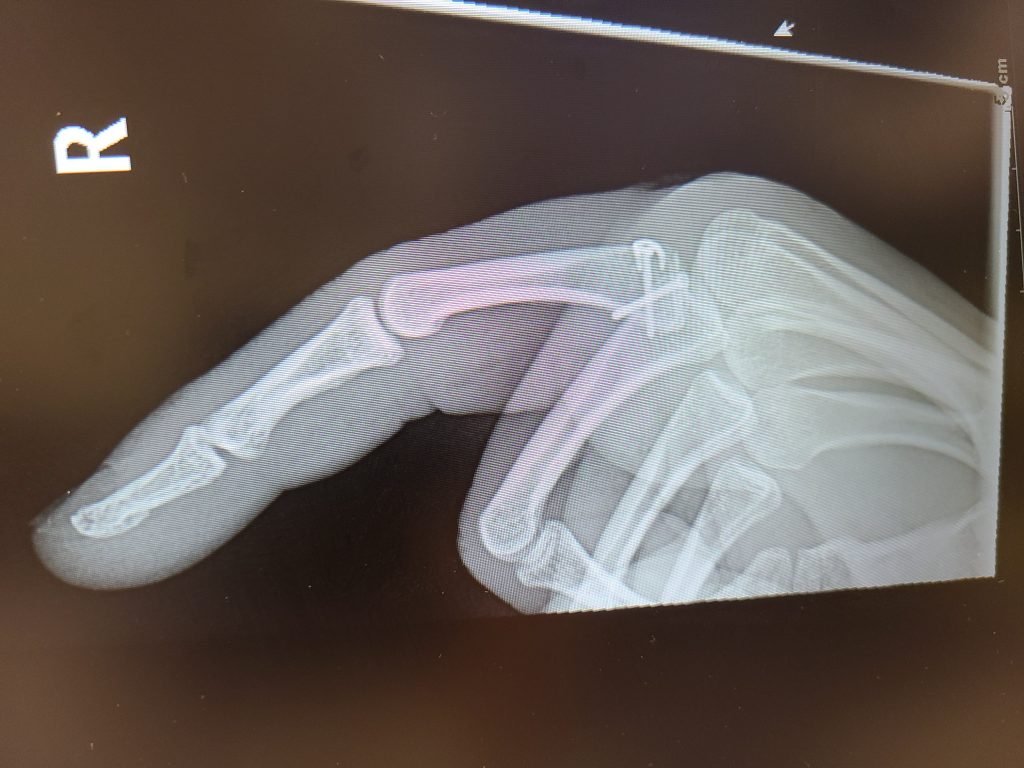

My story begins when my finger was broken one night in April. Wow, that was painful! I then went to the ER and after a couple of x-rays, they confirmed my finger was actually broken. The next phase was to find the best doctor to help fix my broken finger. I had previously been to HSS for my knee and thought there is nowhere else I would go other than HSS. I went through the HSS directory and after a few phone calls to inquire I zeroed in to meet with Dr. Save. I was very impressed with his experience and even more impressed when I met him. I told Dr. Save that I am an avid firearms shooter and that I've been shooting for over 20 years. I take part in shooting competitions all throughout the year and THE most important part of my body is my trigger finger! Dr. Save said that he has a plan to help me get back on track, and I had full confidence that he will. After I woke up from the surgery, he said that it went very well and that we need to start on the road to recovery. I met with Dr. Save all throughout the healing process and each time we met, he was impressed with how well the surgery went and how my finger was healing. Today, I am Back in the Game! I'm at the range every weekend and enjoying every minute of it. My finger is back to normal, I have full range of motion, no pain whatsoever and more importantly my quality of life is back to normal as well. I have 3 small children at home and the day to day of being a dad, a husband, a homeowner and an avid marksman, everything came back to the way it was. I wanted to share my story to let everyone know how thankful I am for Dr. Save and thankful he helped me get back to the things I love the most in life with his incredible gift and talent as a surgeon. Thank you, Dr. Save, you SAVED me! And of course, Thank you HSS!